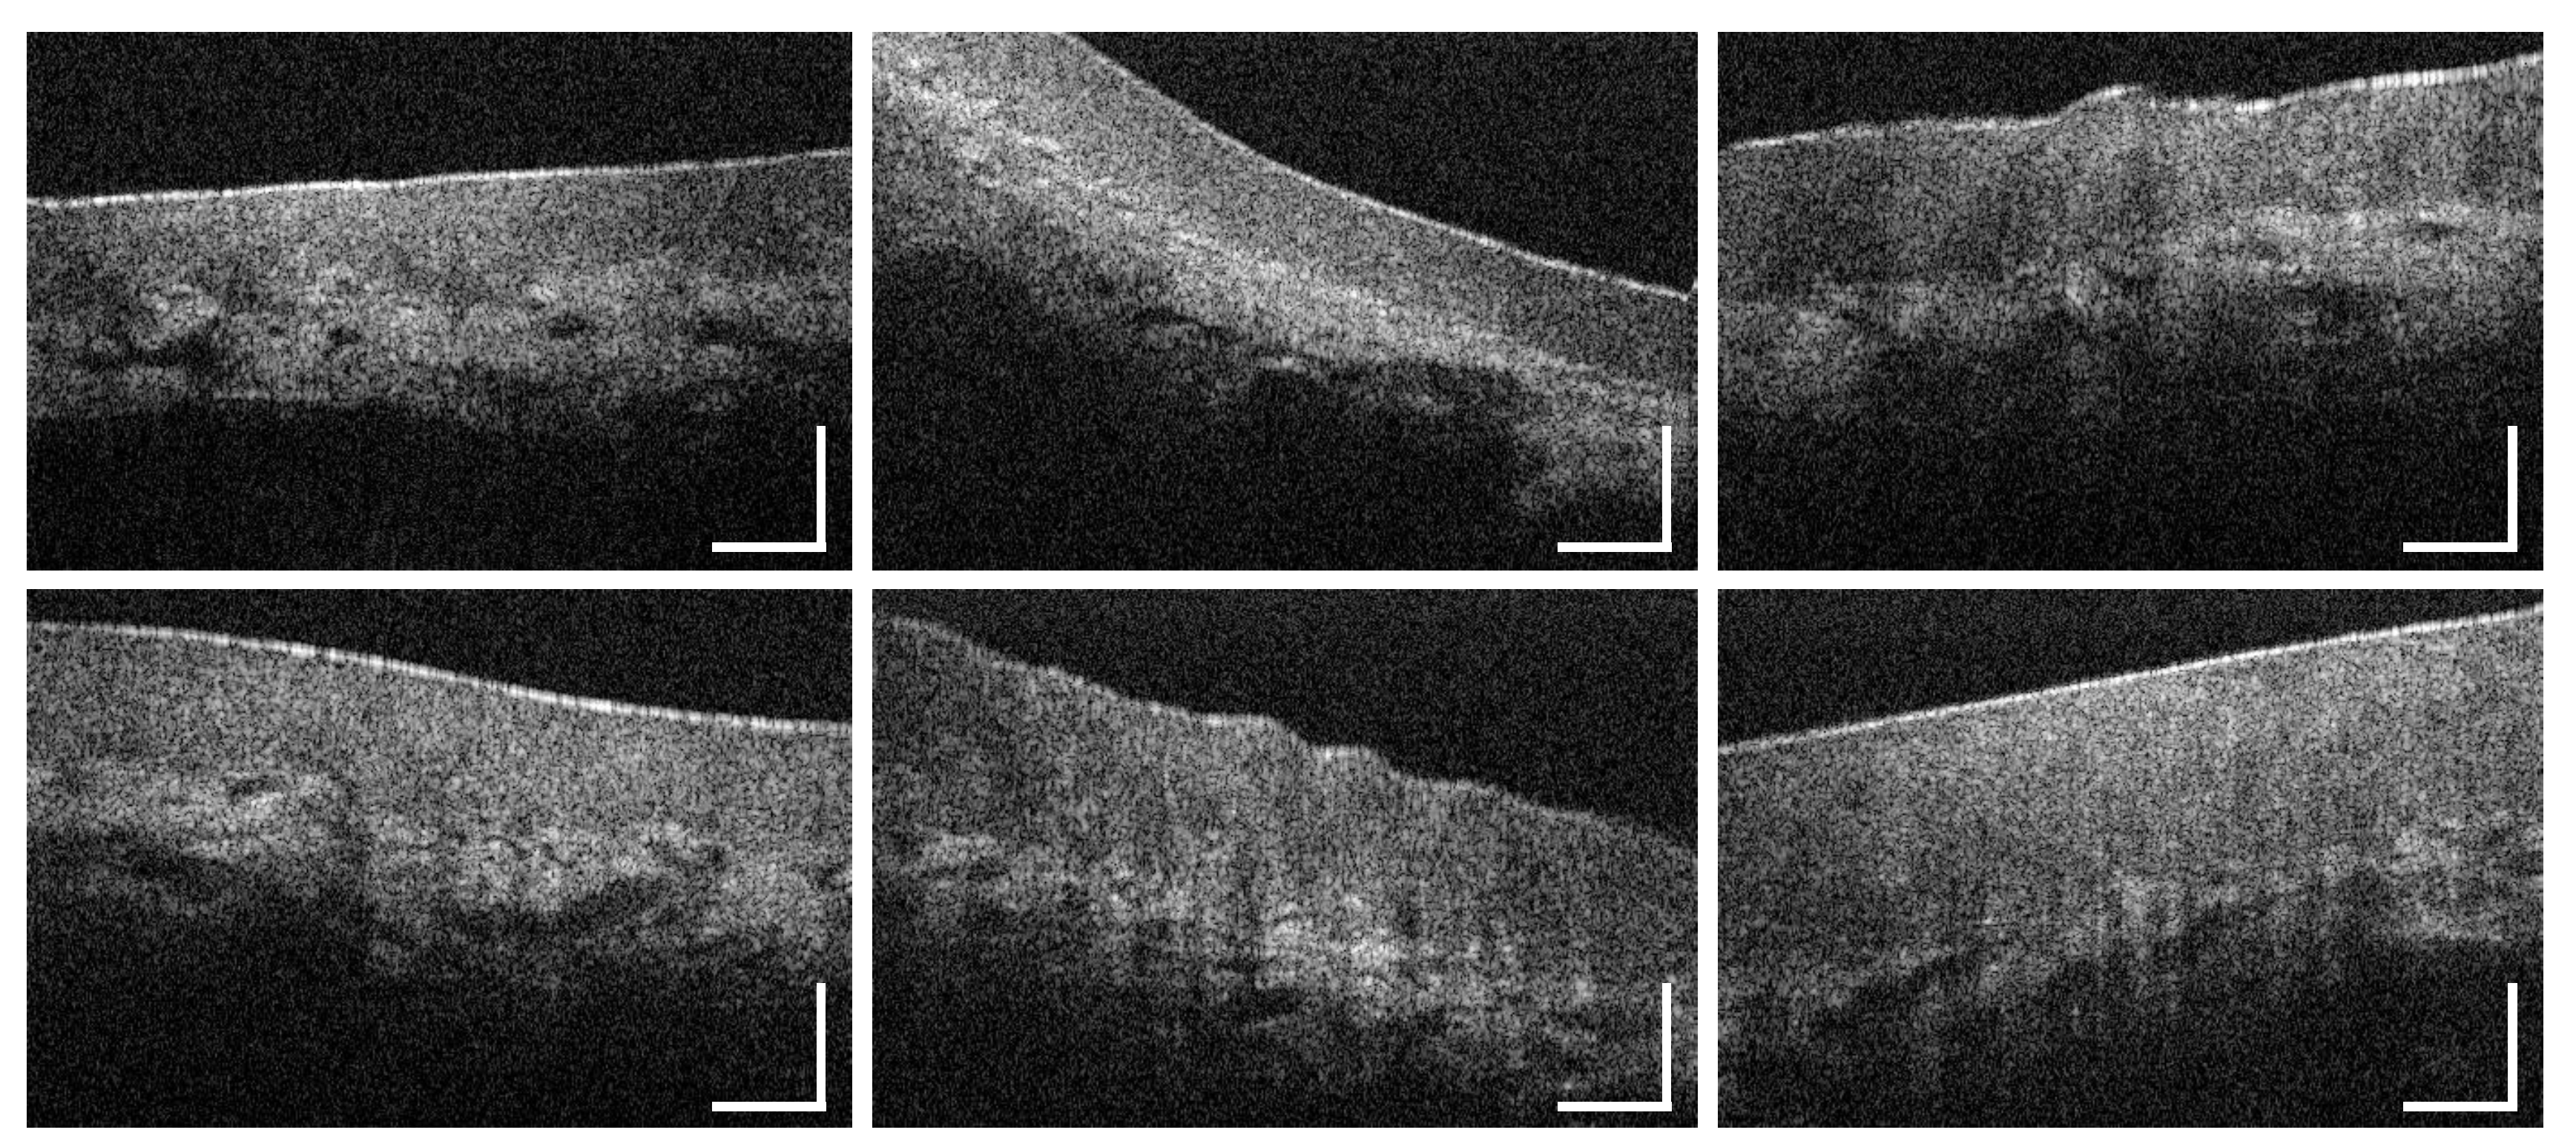

3.5. Soft Palate and Oropharynx

3.6. Palatine Tonsils